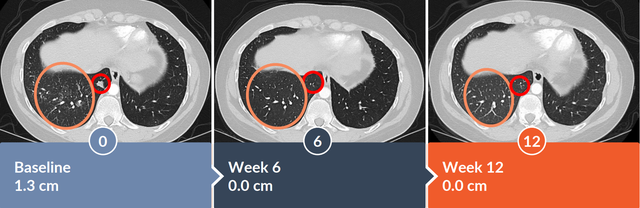

2022年9月,Alaunos Therapeutics在第六届国际癌症免疫治疗会议(CICON)中公布其TCR-T细胞疗法用于晚期非小细胞肺癌患者的病例报告。该患者在6周时达到部分缓解,目标病灶消退46.3%,12周时肿瘤病灶缩小51.2%。患者1为KRAS G12D突变的肺腺癌患者,既往接受手术、化疗、PD-L1抑制剂治疗等,病情进展后接受TCR-T治疗。TCR-T治疗6周后,右下叶肿瘤实现完全缓解(CR)。

TCR治疗12周后,右上肺叶肿瘤也从1.3cm缩小至1.0cm。